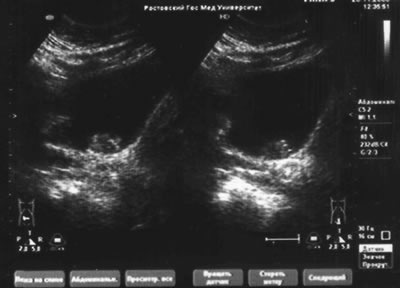

УЗИ мочевой системы – гидронефроза нет, объем мочевого пузыря 300 см3, многофокусный t-r

УЗИ мочевой системы

УЗИ мочевой системы. Рак мочевого пузыря.